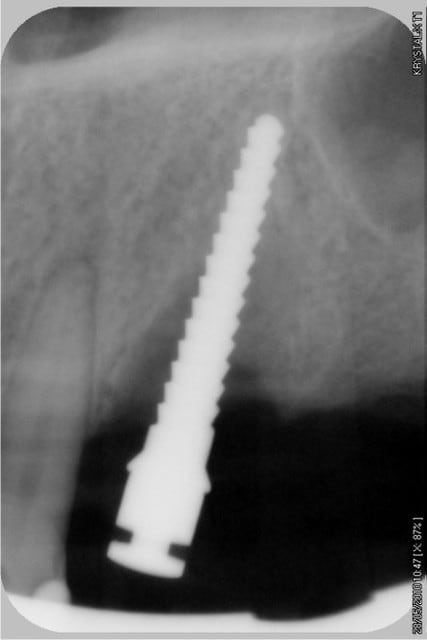

les contrôles radios

--

xbk